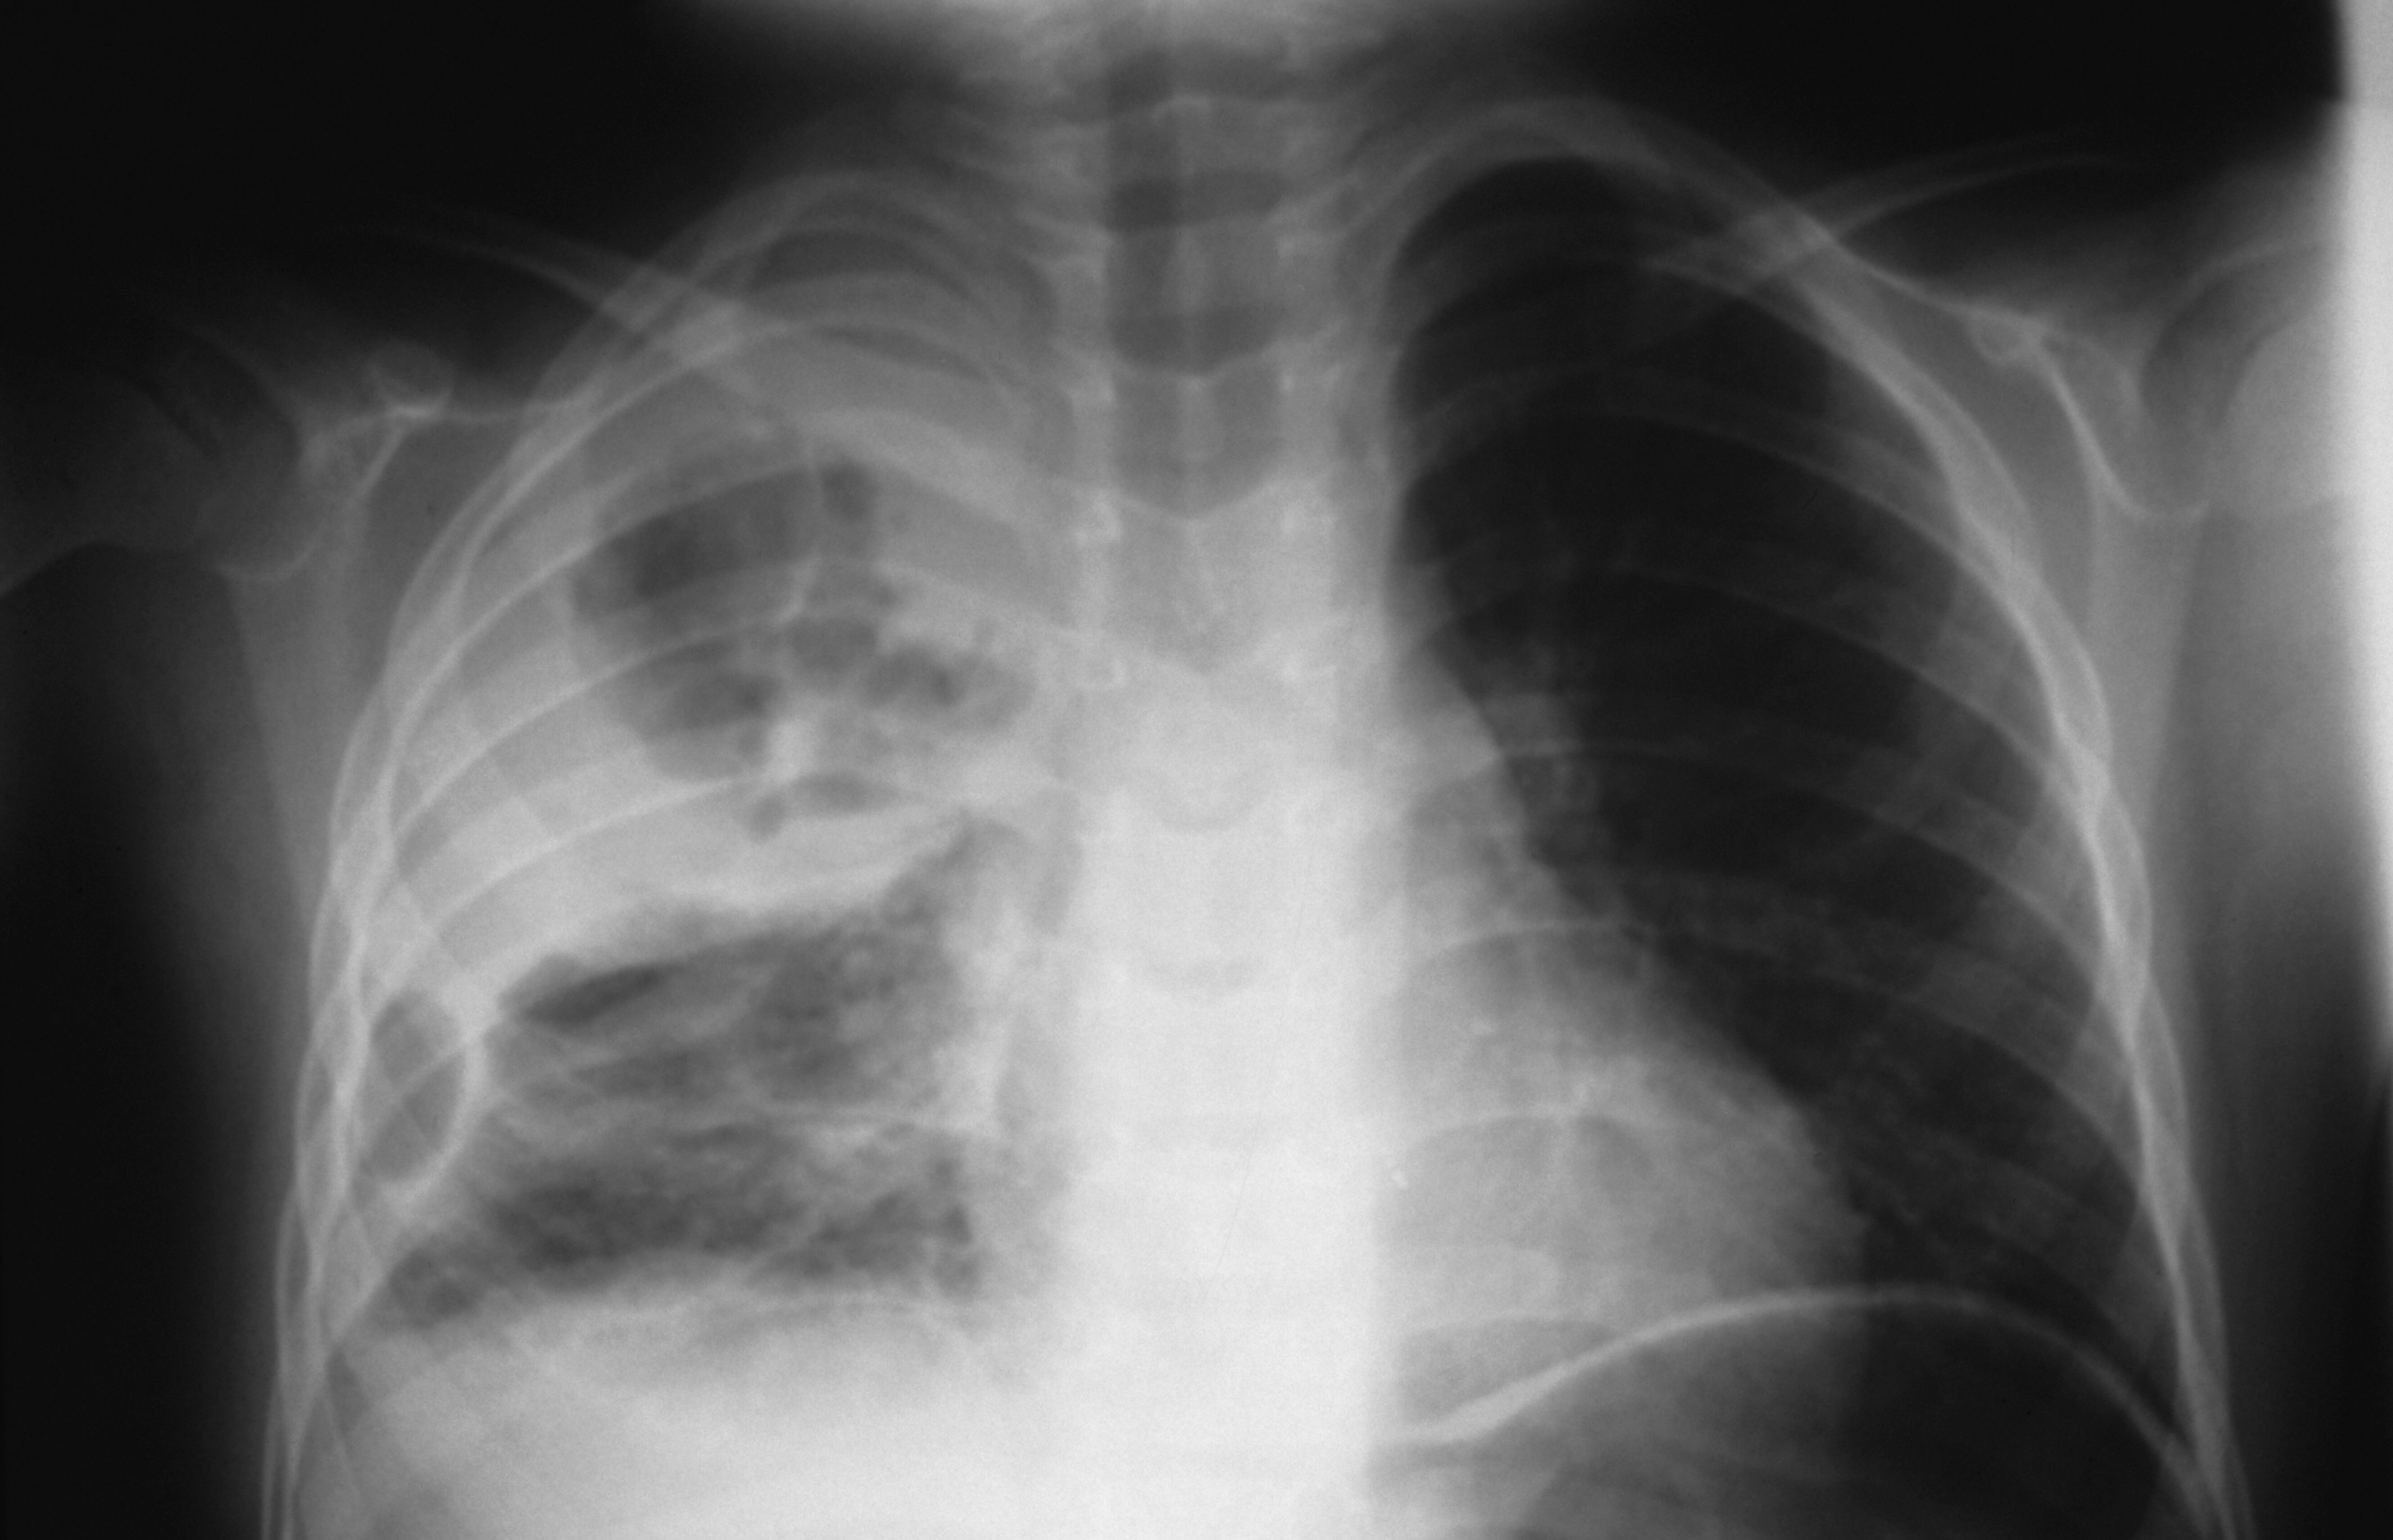

COVID19 vs. Influenza A Chest Xray Comparison Cureus Baby Chest Xray Pneumonia    chest radiographs can show hazy opacities similar to those associated with sdd, coarse irregular opacities similar to those associated with.   chest radiography is the primary imaging study used to confirm the diagnosis of pneumonia. Chest radiograph of left upper lobe pneumonia diagnosed by a paediatric pulmonologist in a 12 month old.   performing chest radiography on pediatric patients. Baby Chest Xray Pneumonia.

Bacterial Pneumonia Chest X Ray vrogue.co Baby Chest Xray Pneumonia  Chest radiograph of left upper lobe pneumonia diagnosed by a paediatric pulmonologist in a 12 month old.   chest radiography is the primary imaging study used to confirm the diagnosis of pneumonia. It is one of the leading causes.  neonatal pneumonia refers to inflammatory changes of the respiratory system caused by neonatal infection.   chest radiographs can show hazy. Baby Chest Xray Pneumonia.